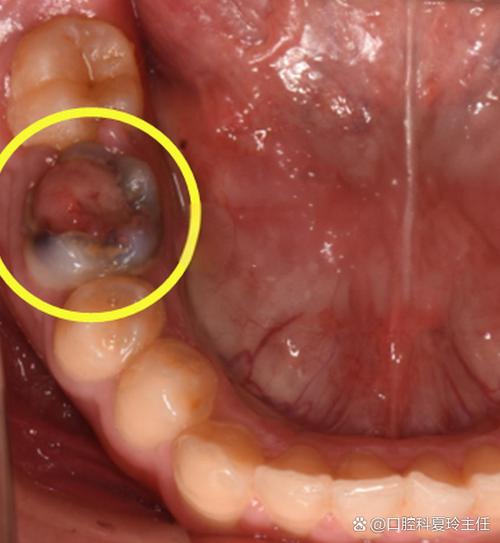

口腔内肉眼可见的病理表现

如果阻生牙部分萌出,可能会在口腔后部牙龈上看到一些异常表现。

肉眼可见的特征:

- 牙龈肿包/脓包: 这是冠周炎的典型表现,部分萌出的牙齿和牙龈之间会形成一个盲袋,食物残渣和细菌容易堆积,难以清洁,当身体抵抗力下降时,就会引发急性炎症,导致牙龈红肿、疼痛,甚至形成脓包,可能伴有口臭、张口受限、发烧等症状。

- 牙龈增生: 长期的慢性刺激可能导致牙龈组织过度增生,覆盖在部分牙冠上,形成一个“小帽子”。

- 牙齿形态异常: 有时萌出部分可能很小,或者形态不正常。